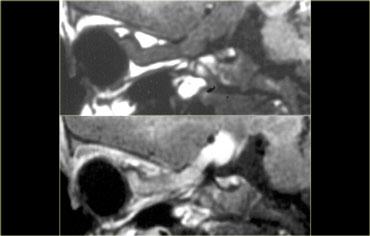

Bác sĩ phẫu thuật thần kinh đã chỉ định chụp MRI này.

Tổn thương nằm một phần trong xoang hang phải và một phần trong hố yên có tín hiệu chủ yếu là đen trên chuỗi xung T1W này.

Nhìn chung, có ba thứ cho tín hiệu đen trên MRI: không khí, xương và dòng máu chảy nhanh. Trong trường hợp này, tín hiệu đen là do dòng máu chảy nhanh trong túi phình động mạch cảnh.

Đây là hình chụp mạch máu (angiogram) tương ứng.

Rõ ràng, đây không phải là tổn thương có thể phẫu thuật qua đường xuyên bướm (transsphenoidal)!

Bên trái là hình ảnh chuỗi xung T1W của một túi phình huyết khối hóa với tín hiệu cao trên chuỗi xung không tiêm thuốc tương phản từ.

Túi phình xuất phát từ đoạn trong xoang hang của động mạch cảnh trong phải.

Bên phải là hình ảnh chuỗi xung T2W: túi phình huyết khối hóa có viền tối xung quanh.

Đây là ví dụ về một túi phình huyết khối hóa một phần nằm trong bể trên yên (suprasellar cistern).

Lòng mạch còn thông (patent lumen) có tín hiệu đen trên các chuỗi xung T1W này.

Xung quanh lòng mạch là các lớp cục máu đông ở nhiều giai đoạn khác nhau, sắp xếp thành từng lớp từ lòng mạch đến thành túi phình.

Hình ảnh này trông giống như một củ hành tây cắt đôi.